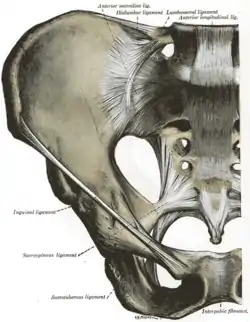

Articulations of pelvis. Anterior view.

Articulations of pelvis. Anterior view. The superficial branches of the internal pudendal artery.